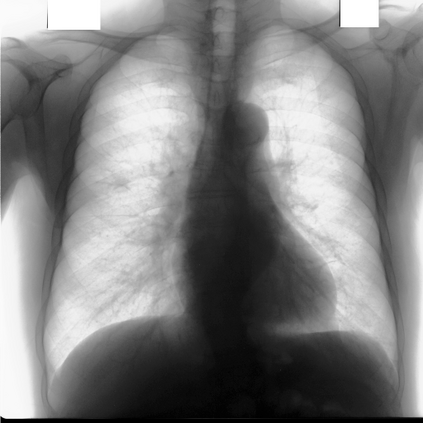

Multi-organ segmentation of X-ray images is of fundamental importance for computer aided diagnosis systems. However, the most advanced semantic segmentation methods rely on deep learning and require a huge amount of labeled images, which are rarely available due to both the high cost of human resources and the time required for labeling. In this paper, we present a novel multi-stage generation algorithm based on Generative Adversarial Networks (GANs) that can produce synthetic images along with their semantic labels and can be used for data augmentation. The main feature of the method is that, unlike other approaches, generation occurs in several stages, which simplifies the procedure and allows it to be used on very small datasets. The method has been evaluated on the segmentation of chest radiographic images, showing promising results. The multistage approach achieves state-of-the-art and, when very few images are used to train the GANs, outperforms the corresponding single-stage approach.